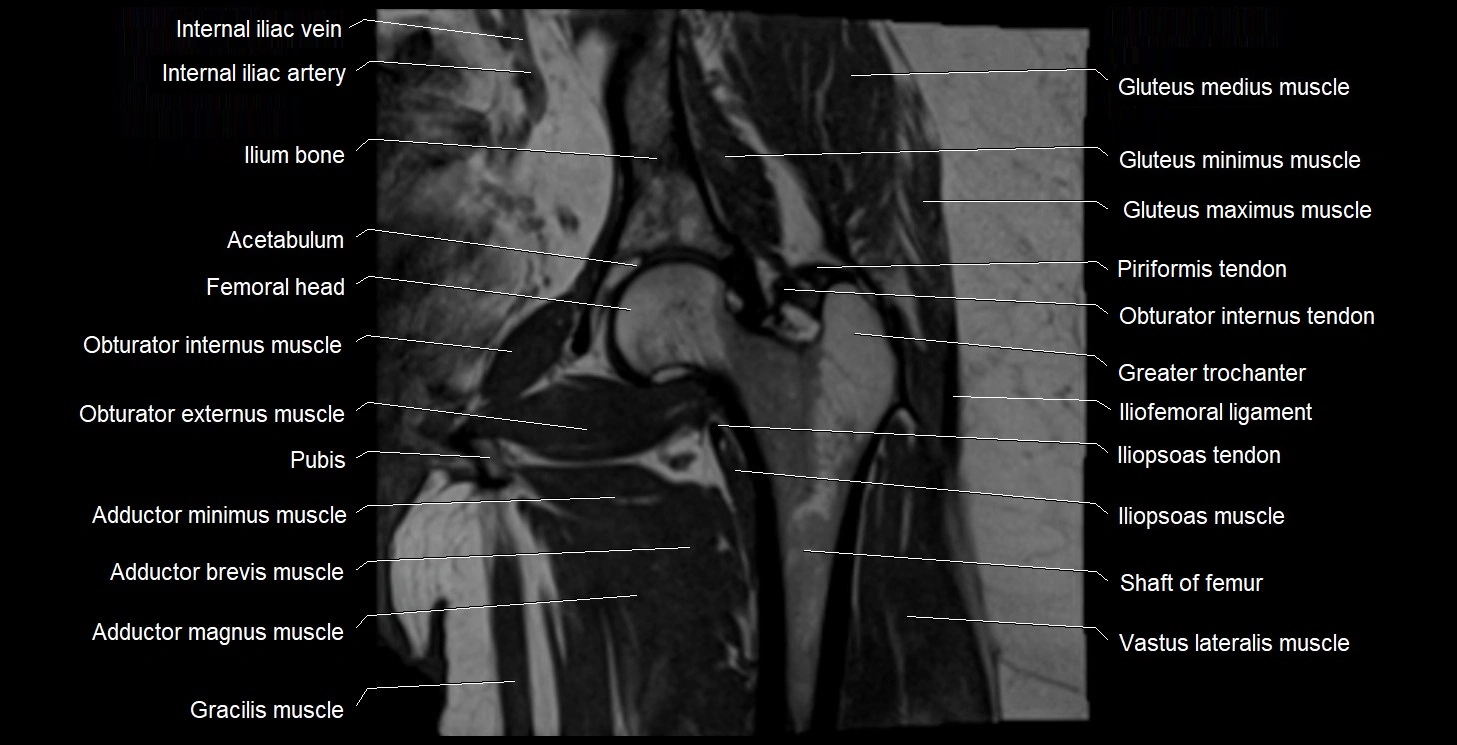

- Acetabulum

- Gluteus maximus muscle

- Gluteus medius muscle

- Gluteus minimus muscle

- Greater trochanter

- Head of femur

- Iliofemoral ligament

- Iliopsoas muscle

- Iliopsoas tendon

- Ilium bone

- Internal iliac artery

- Obturator internus muscle

- Obturator internus tendon

- Pectineus muscle

- Pubic bone

- Vastus lateralis muscle